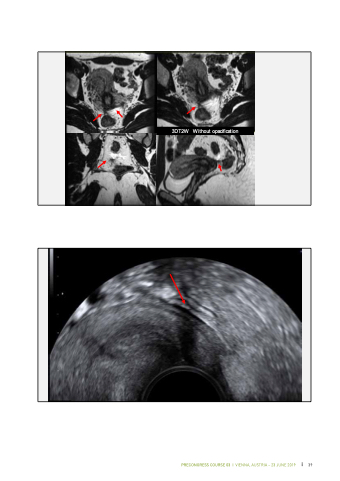

3DT2W Without opacification